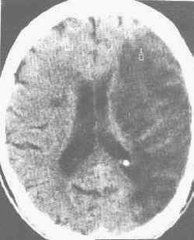

腔隙性腦梗死病灶的大小與腦電圖的異常率:有關如病灶為1.5~3mm者45%有異常如小於1.5mm則65%腦電圖正常;